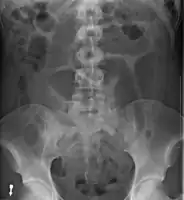

After taking a thorough history, the diagnosis of colonic volvulus is usually easily included in the differential diagnosis. Abdominal plain x-rays are commonly confirmatory for a volvulus, especially if a "bent inner tube" sign or a "coffee bean" sign are seen. These refer to the shape of the air filled closed loop of colon which forms the volvulus. Should the diagnosis be in doubt, a barium enema may be used to demonstrate a "bird's beak" at the point where the segment of proximal bowel and distal bowel rotate to form the volvulus.